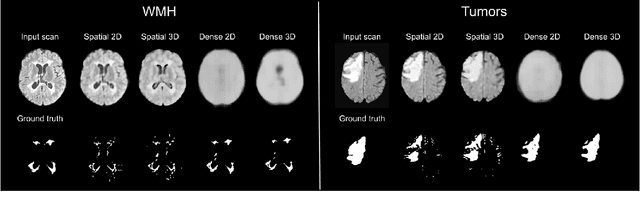

Abstract:Automatic segmentation of brain abnormalities is challenging, as they vary considerably from one pathology to another. Current methods are supervised and require numerous annotated images for each pathology, a strenuous task. To tackle anatomical variability, Unsupervised Anomaly Detection (UAD) methods are proposed, detecting anomalies as outliers of a healthy model learned using a Variational Autoencoder (VAE). Previous work on UAD adopted a 2D approach, meaning that MRIs are processed as a collection of independent slices. Yet, it does not fully exploit the spatial information contained in MRI. Here, we propose to perform UAD in a 3D fashion and compare 2D and 3D VAEs. As a side contribution, we present a new loss function guarantying a robust training. Learning is performed using a multicentric dataset of healthy brain MRIs, and segmentation performances are estimated on White-Matter Hyperintensities and tumors lesions. Experiments demonstrate the interest of 3D methods which outperform their 2D counterparts.